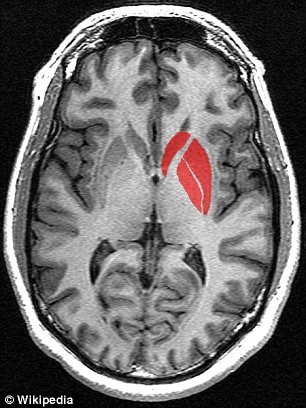

研究の結果、エ〇チな動画をたくさん見た人は脳の刺激中枢部分が委縮した脳をしています。

研究者たちは「エ〇チな動画をたくさん見た人の場合、脳の領域の中で刺激と報酬反応を司る線条体が委縮していることが確認できた」という衝撃的な結果を伝えました。

<健常者の脳>

<ポ〇ノ中毒者の脳>